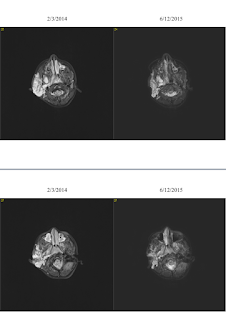

I’m going to show one more set of

pictures—it’s a bit confusing at first if you are not used to looking at MRIs, but

what follows is a side-by-side images of the same slice of Jane’s tumor from

2/2014 compared with now. Tumor is the

big white blob on the left of the image.

You can see in some spots where it appears to have just melted! (You can also see from these images why her

tumor can’t be surgically removed—it wraps around everything.)